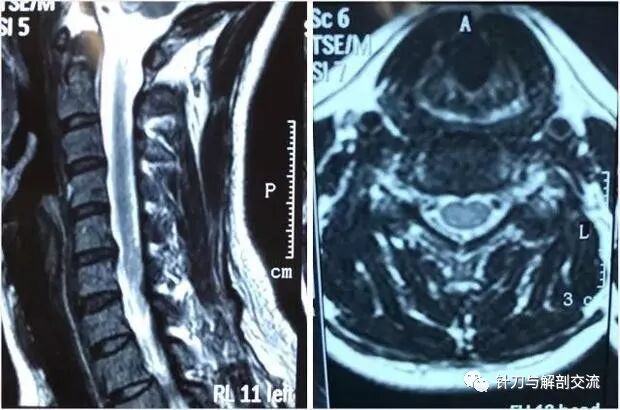

颈椎磁共振表现为:颈椎间盘突出,脊髓受压。

辅助检查:颈椎正侧位片:生理曲度变直,颈部脊柱向左侧弯,寰枕间隙变窄、C3/4钩椎关节变尖。颈椎磁共振:C5/6椎间盘轻度突出。